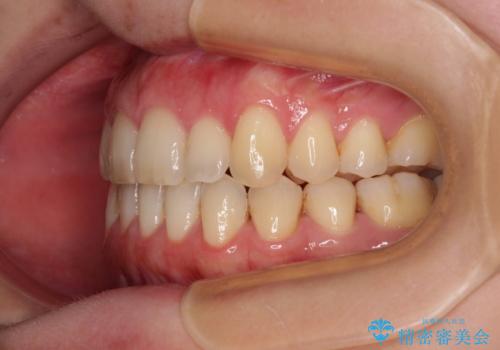

- 上下前歯の隙間を気にして来院された患者様です。

下顎前歯が1本欠損しており、上下小臼歯はクロスバイトとなり、上下前歯の接触もないという不正咬合の状態でした。

クロスバイトはワイヤー矯正が得意とするところであり、上下前歯の非接触や開咬はインビザラインの得意とするところであるので、ワイヤー装置により事前にクロスバイトを改善し、その後にインビザラインにて仕上げていくこととしました。